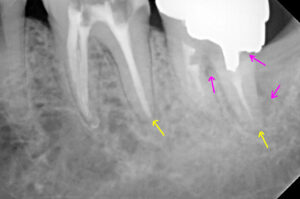

2017年8月 再来時に左下第二大臼歯のレントゲン

を撮り処置途中歯の被せ物の相談をするもそのままに

2019年7月になってやっとご本人が処置の決断をされ

根の処置が上手くいかないことを説明し、保険で

土台と冠を被せることで納得していただきました。

レントゲンでは神経の詰め物の状態の違い→

歯根の崩壊度は経時的なもの?→